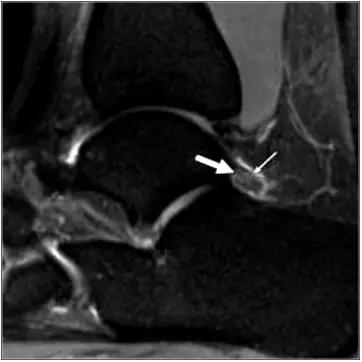

- 影像学表现为距骨后三角骨的存在或损伤以及距骨后突骨赘形成,导致踝关节跖屈受限,可伴随拇长屈肌肌腱鞘炎症及邻近滑膜不同程度的炎性增生 。

正常后踝韧带;MRI 冠状位T2-FLAIR示踝间后韧带(长箭)

- MRI 检查示距后三角骨及周围软组织有水肿信号,距后三角骨和距骨之间正常的低信号纤维连接中断,出现液性信号。

3、MR表现:

- 三角籽骨或距骨后三角结构模糊和变形,T1WI信号降低, T2WI信号升高,

- 周围脂肪水肿,

- 踇趾长屈肌腱信号升高,见鞘膜积液,

- 胫骨后下跟骨上缘骨结构形态变化和信号异常,

- 三角籽骨和距骨退行性囊变。